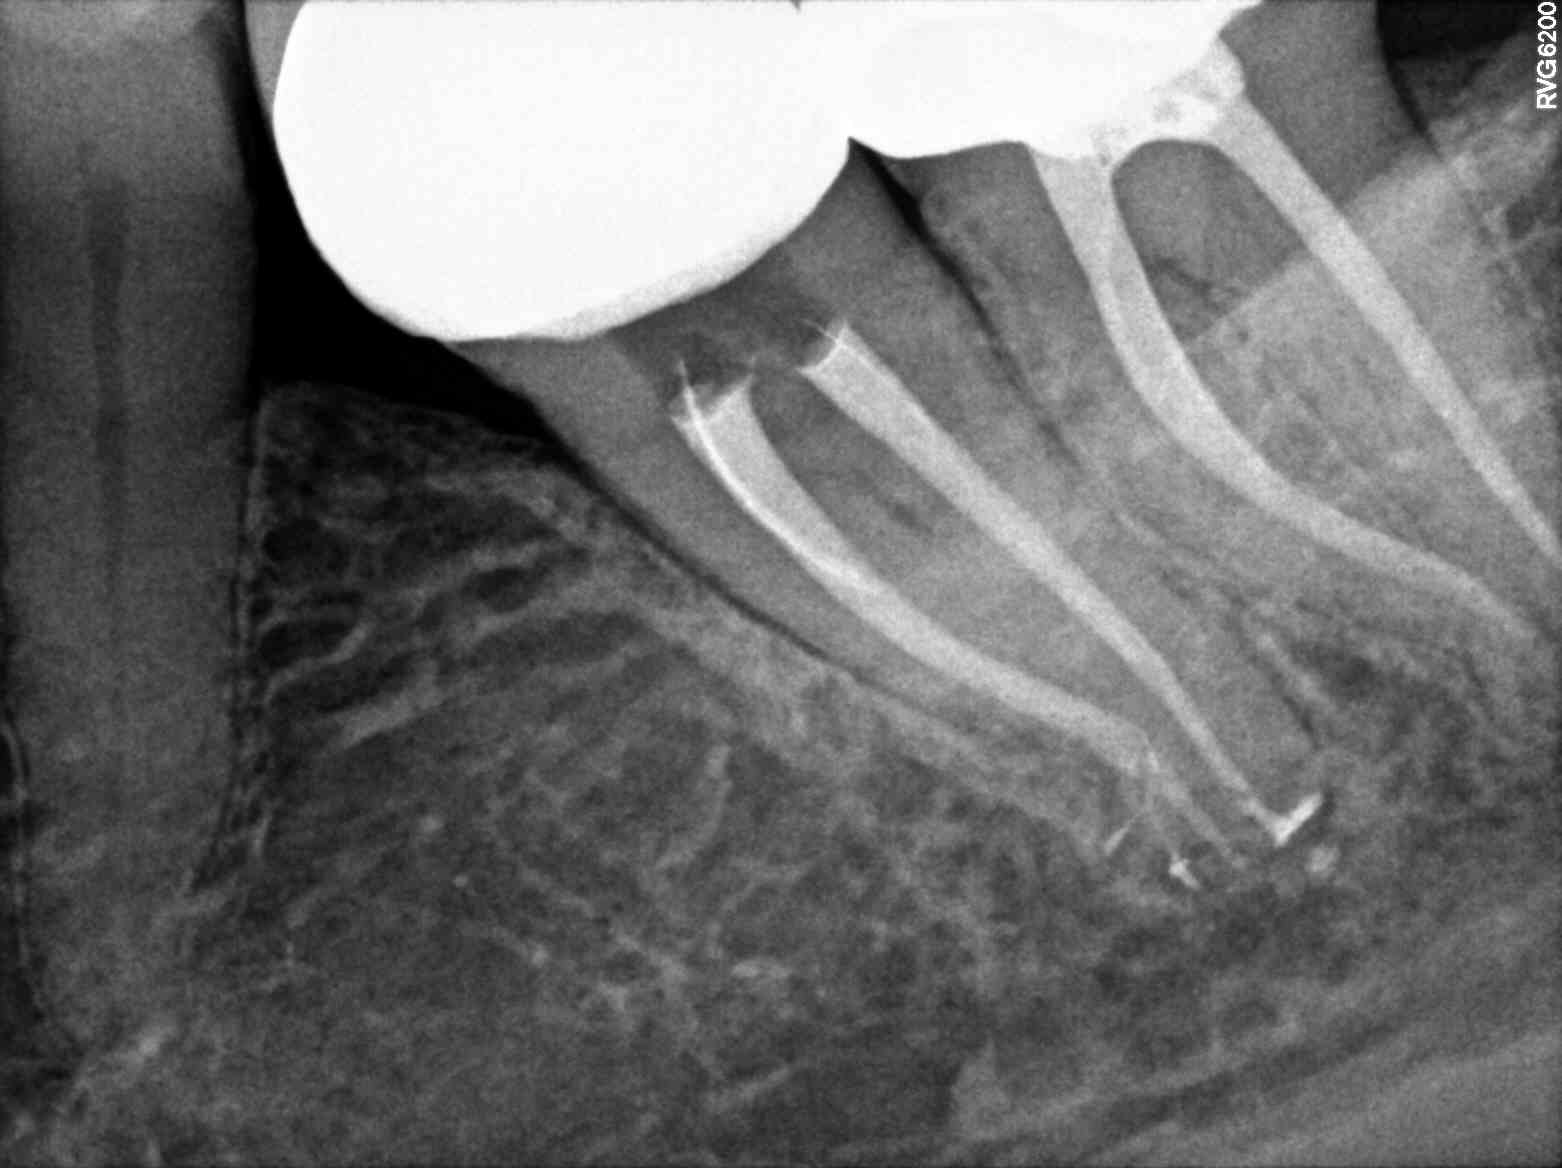

From master-endodoncia.blogspot.com

Master Endodoncia Caso clínico Master Molar Prenavideño Stop Apical Endodoncia The data presented in this review can aid in. Stephen buchanan and christophe verbanck say that minimally invasive endodontics can be. Root canal shaping in the age of minimally invasive endodontics (mie) technology. The extent of apical enlargement can impact the outcome of endodontic treatment. The concept of instrumentation beyond the apical foramen by small flexible file. This retrospective study. Stop Apical Endodoncia.